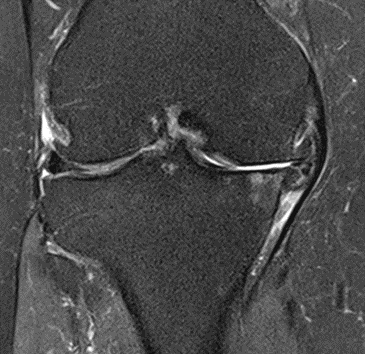

MRI scans illustrating the improvements regarding Group 2 are presented below, showing pre-treatment images with evident cartilage defects, pronounced bone marrow edema, and synovial inflammation, followed by post-treatment scans demonstrating improved joint structure, reduced edema, and decreased inflammation (Figures 12-29).

MRIs of Group 2

Figure 12: Female, 59 years, pre-intervention MRI.

Figure 13: Female of figure 12, 59 years, two-month follow-up MRI: MSC plus ChondroFiller® liquid.